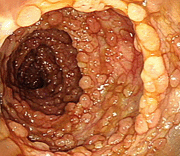

대장암의 대장내시경 소견 이미지

[대장암의 대장내시경 소견]